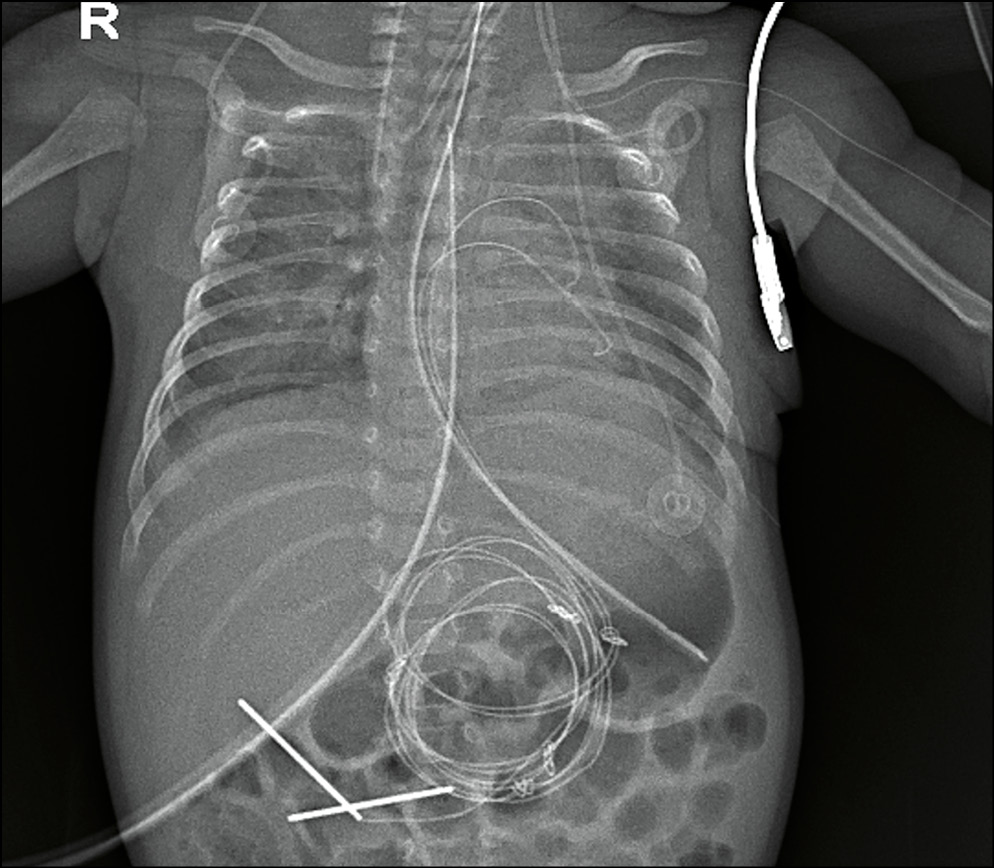

Рис. 1. Пациент с врожденным пороком сердца, частичным аномальным дренажем легочных вен, легочной гипертензией и дыхательной недостаточностью. Исследование выполнено при помощи микрофокусного рентгеновского аппарата.

Fig. 1. Patient with CHD, anomalous pulmonary venous connection, pulmonary hypertension and respiratory failure. Mi-crofocal X-ray device.

Рентгенография органов грудной клетки традиционно является наиболее важной в оценке легочной паренхимы у детей раннего возраста: зачастую лечащие врачи назначают выполнение торакоабдоминальной рентгенограммы для одномоментного исследования органов грудной и брюшной полости. Наиболее важной задачей при исследовании органов грудной клетки является непосредственно оценка паренхимы легких, ее пневматизация и наличие участков затенения. Необходимо отметить изменения со стороны легочного рисунка — усиление, сгущение, деформацию или его обеднение. Необходимо оценить уровень положения диафрагмы и состояние реберно-диафрагмальных синусов, а также положение зондов, дренажей и катетеров (рис. 2).